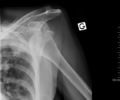

خلع سفلي للذراع بعد حادث سيارة. لاحظ كيفية بروز عظمة العضد. كما يظهر أيضاً كسر في الحدبة الكبرى.

الخلع السفلي هو النوع الأقل شيوعاً، ويحدث في أقل من 1% من الحالات. تسمى هذه الحالة بالخلع المنتصب لأن المصاب غالباً ما يظهر ممسكاً بذراعه إلى الأمام أو إلى أعلى الرأس.[14] يحدث الخلع السفلي بسبب جذب الذراع بقوة مما يجبر عظمة العضد على الخروج من الأخرم.[15] تصاحب هذه الحالة أضرار بالغة في الأعصاب، الأوعية الدموية، أوتار العضلات، الأربطة حسب آلية الاصابة.